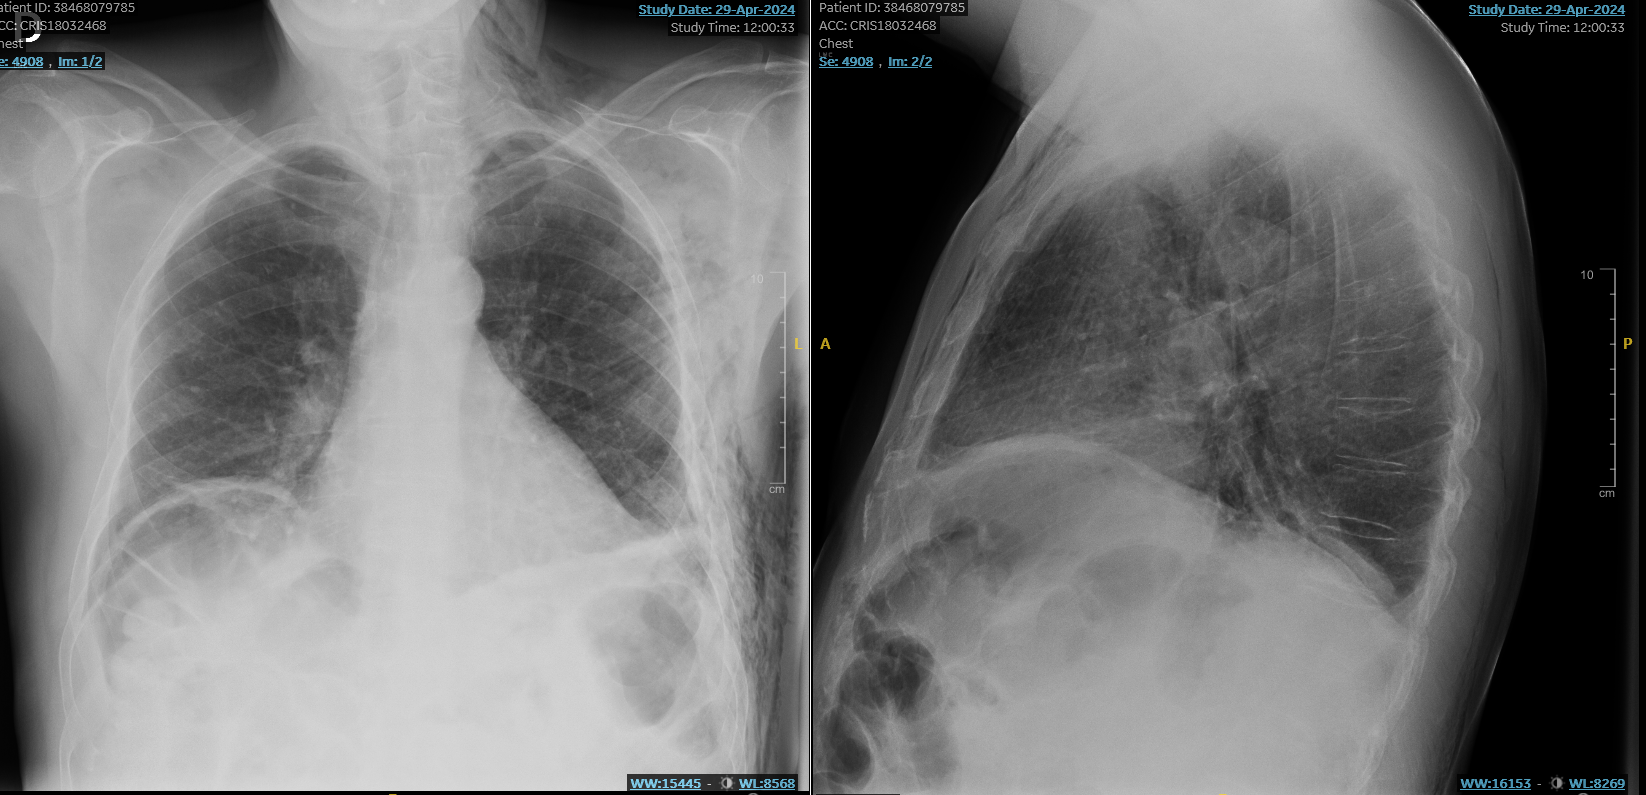

Rx Tórax: múltiples fracturas costales con pinzamiento seno costrofrénico izquierdo.

TAC Tórax: fracturas costales 8ª a 11ª, 2 con desplazamiento.

Se confirman laos hallazgos tanto por Rx como TAC Tórax: Fracturas costales izquierdas de 8ª a 11ª con leve neumotórax anteroizquierdo con Atelectasia laminar y opacidades subpleurales izquierdas con Enfisema subcutáneo. Buena evolución posterior con controles periódicos en C.S. con Ecografía Pulmonar.